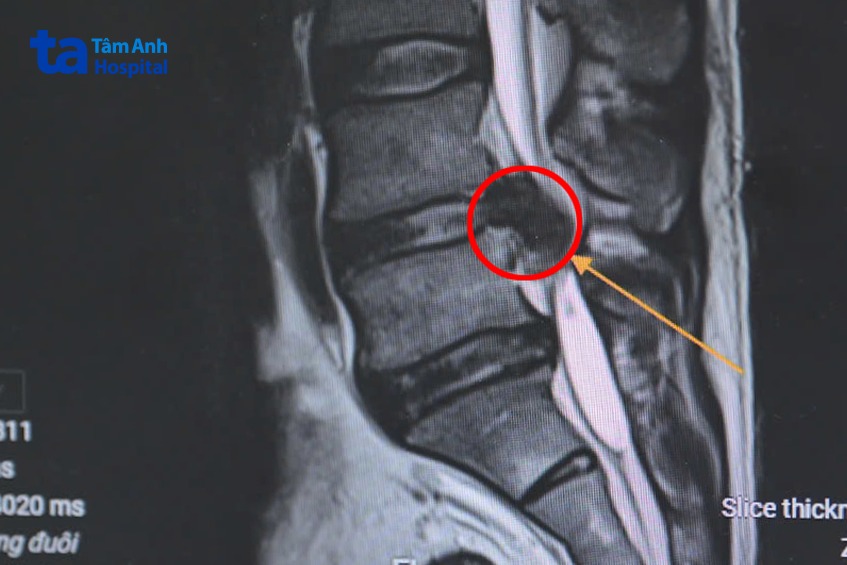

ThS.BS Phạm Văn Tín, khoa Ngoại Thần kinh – Cột sống, Bệnh viện Đa khoa Tâm Anh Hà Nội cho biết, người bệnh nhập viện trong tình trạng yếu liệt 2 chân, rối loạn đại tiểu tiện, ứ đọng nước tiểu bàng quang, run và sốt cao. Các bác sĩ khoa Cấp cứu lập tức cho người bệnh thuốc giảm đau và đặt ống sonde tiểu tạm thời để dẫn lưu nước tiểu ra ngoài. Sau đó, các bác sĩ chỉ định chụp MRI, X-Quang và một số xét nghiệm cận lâm sàng khác nhằm xác định chính xác vị trí tổn thương. Kết quả MRI cho thấy người bệnh có khối thoát vị lớn (kích thước (2×2 cm) ngang mức L4-5 chiếm gần hết ống sống, chèn ép nặng các rễ thần kinh ngang mức (còn được gọi là chùm đuôi ngựa). Đây là nguyên nhân khiến người bệnh đại tiểu tiện không tự chủ, hai chi tê yếu không thể đi lại. Bác sĩ kết luận người bệnh bị thoát vị đĩa đệm biến chứng chèn ép chùm đuôi ngựa.